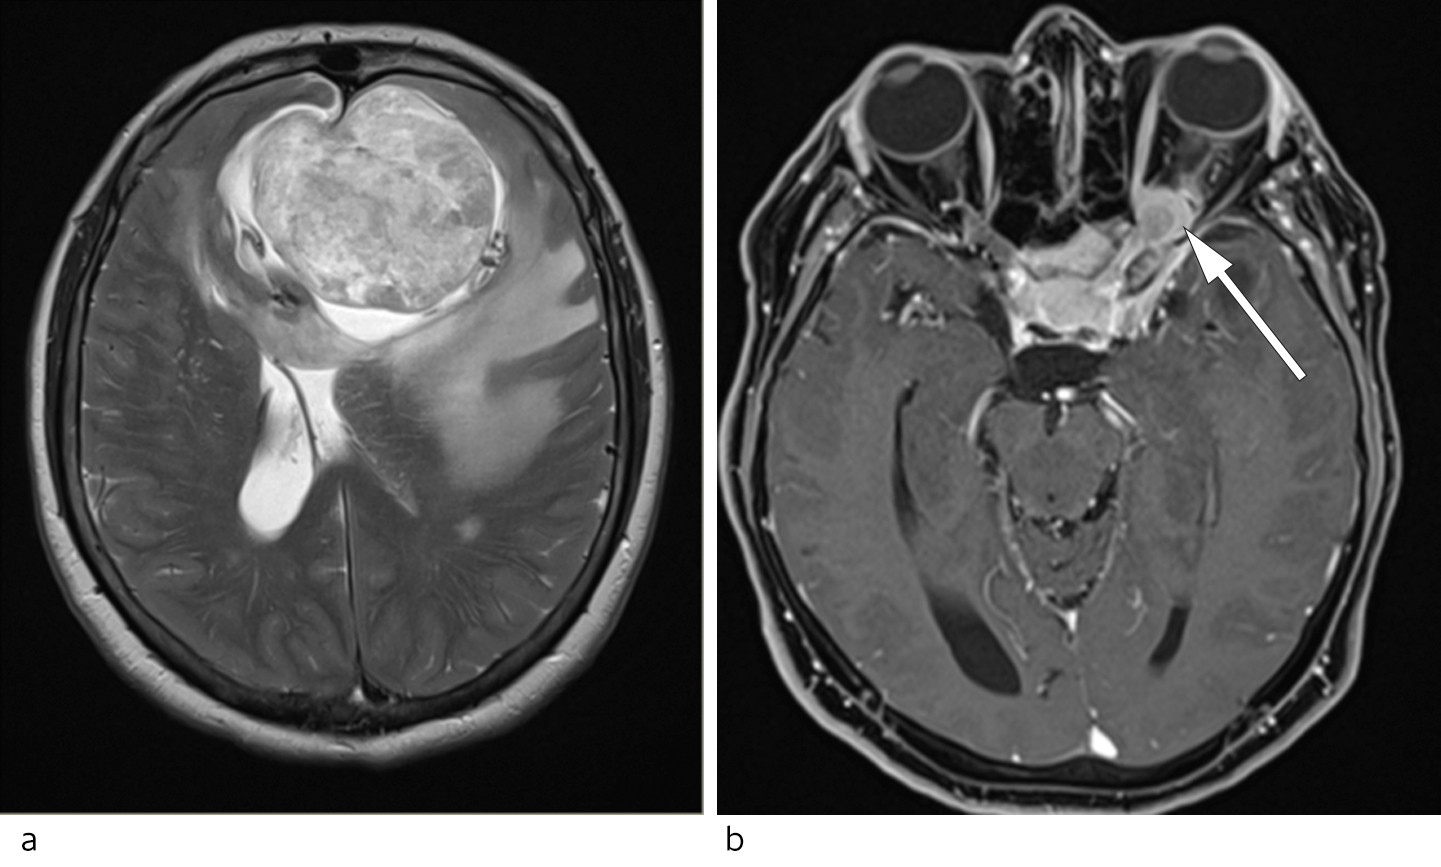

Pasienten var ikke til ytterligere øyeundersøkelser før det aktuelle, 40 år etter at hun gradvis hadde mistet synet på venstre øye. Til tross for subjektiv synsreduksjon hadde pasienten visus 1,0 på høyre øye, og hun kunne lese alle Ishiharas fargeplansjer. Perimetri viste imidlertid et synsfeltutfall som var mest uttalt i øvre temporale kvadrant. Venstre øye var som tidligere blindt. Ved oftalmoskopi ble det funnet høyresidig papillødem (figur 1a). Som ved tidligere undersøkelser var venstre papill blek med slyngede blodkar (figur 1b). På  mistanke om kompresjon av høyre synsnerve ble det rekvirert MR av hodet og orbita med gadolinium-kontrastmiddel. Bildene viste en 5,5 × 5,5 × 6,5 cm stor, ekstraaksial, kontrastladende tumor med basis i fremre skallegrop. Tumoren hadde venstresidig overvekt, men bredte seg langs dura i skallebasis bilateralt og ga betydelig lokal masseeffekt (figur 2a). Det forelå også innvekst i venstre optikuskanal og kompresjon av venstre synsnerve (figur 2b). Nevroradiologisk diagnose var meningeom.

Et viktig nevrooftalmologisk prinsipp er at døde aksoner ikke utvikler ødem. Sykdommer som normalt forårsaker hevelse i synsnerven, vil ikke nødvendigvis gjøre det om synsnerven er atrofisk. Kombinasjonen av ipsilateral papillatrofi og kontralateralt papillødem kan oppstå der en frontal sykdomsprosess først ensidig presser mot én synsnerve slik at denne atrofierer, og deretter forårsaker intrakraniell trykkstigning og stase i den andre synsnerven. Den atrofiske synsnerven kan også ha såkalte optociliære shuntkar, som indikerer kronisk obstruksjon av den sentrale retinalvenen (1). Denne konstellasjonen av oftalmologiske funn som følge av en frontal hjernetumor eller abscess ble beskrevet av Robert Foster Kennedy i 1911 og omtales derfor som Foster Kennedys syndrom (2).